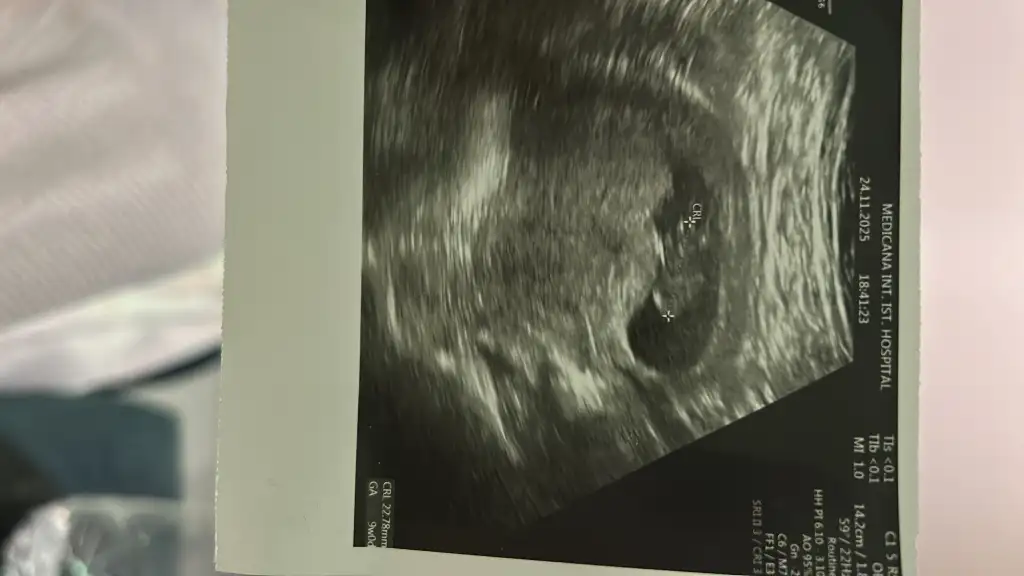

Merhaba arkadaşlar ben de haziranda doğum yapacağım ikili test yaptırdık bir problem çıkmadı fetal dna da yaptıracağız biz. Şu an 13+3 haftalık hamileyim ☺️ cinsiyet tahmini yapabilir misiniz ? Doktorumuz bir tahminde bulundu ama net bir şey diyemem dedi yüzdelik bile belirtmedi 10 ve 13. Haftalık fotoğraflarını bırakıyorum